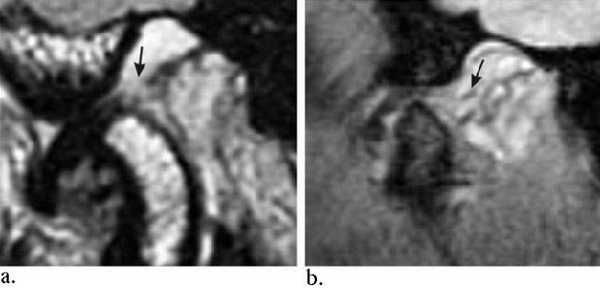

Заднее смещение диска.

Заднее смещение диска (составляет менее 0,01% всех патологий ВНЧС).

А. Положение с закрытым ртом. Суставной диск сместился дорзально.

Б.Положение с открытым ртом. Возвращение суставного диска на уровень мыщелка нижней челюсти. Движения челюсти очень ограничены в данном случае.